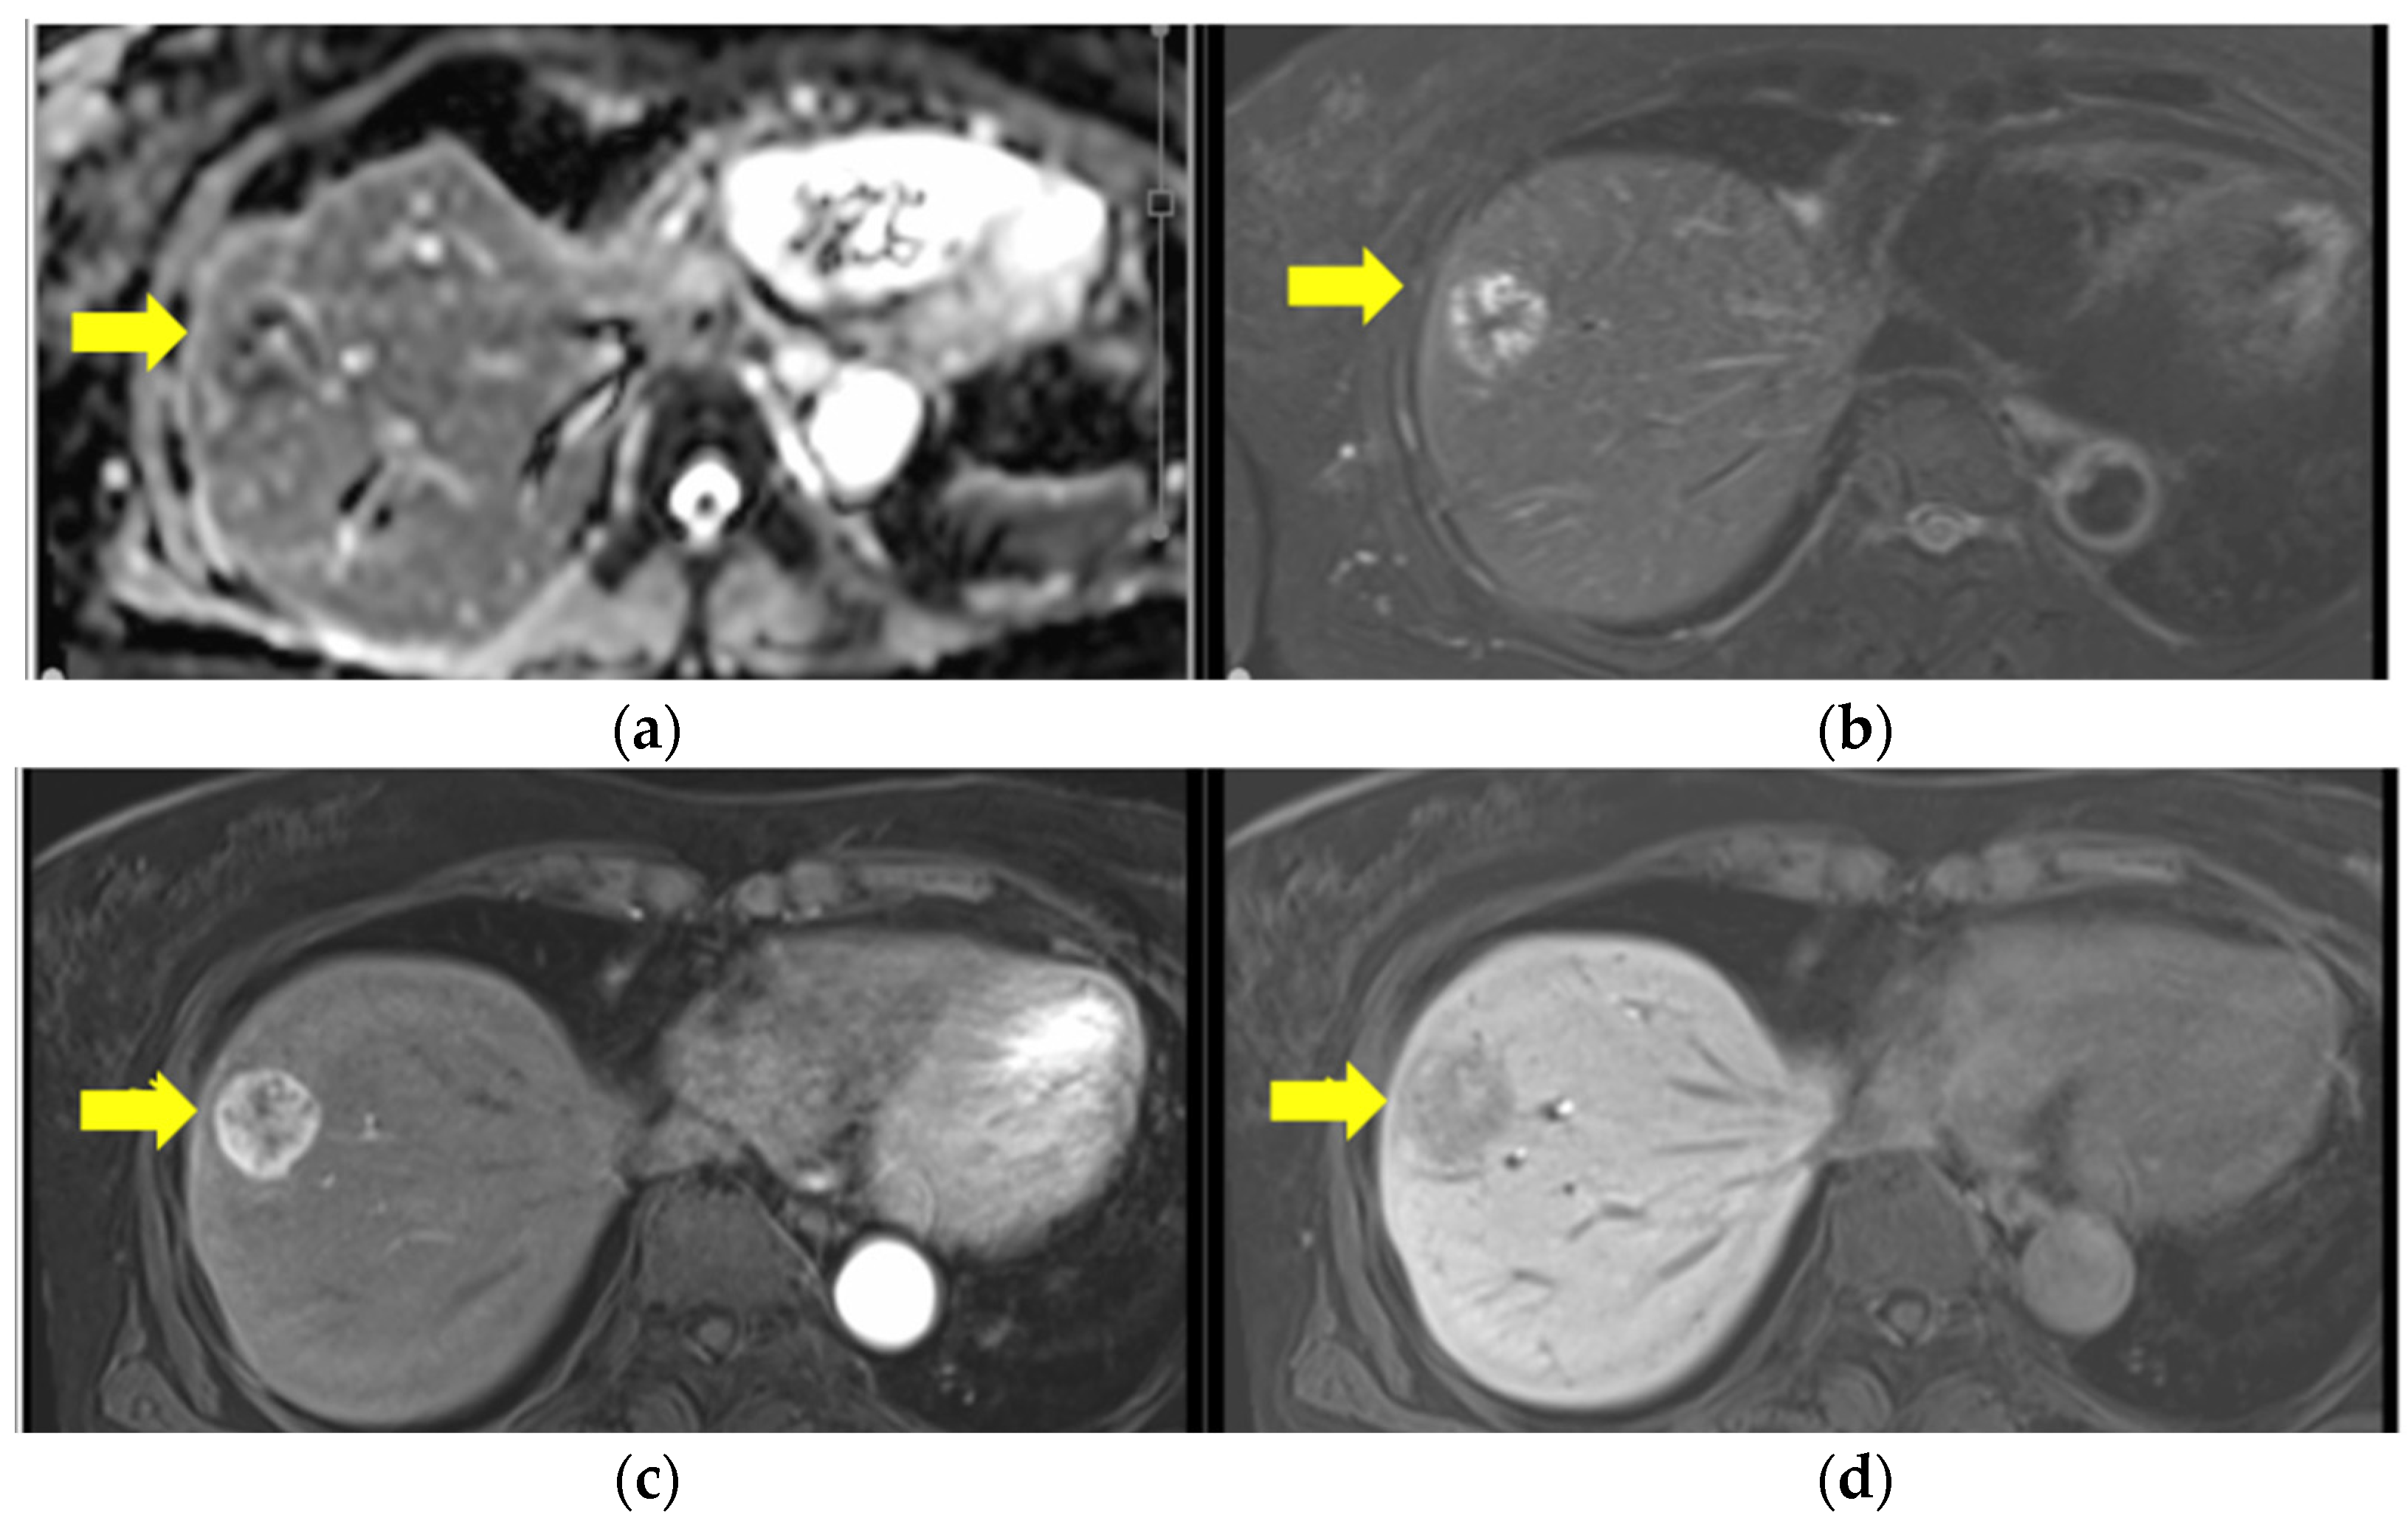

2. Case Report